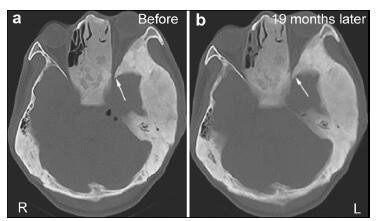

20161117201145  Figure 5 (a, b) CT showing the left optic canal before and nineteen months after surgery (arrows). The compression of the left optic nerve was more severe at nineteen months after surgery (right) than before surgery (left).